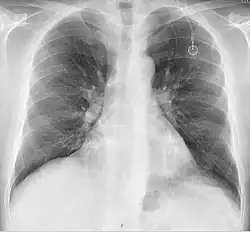

The port is usually inserted in the upper chest (known as a "chest port"), just below the clavicle or collar bone, with the catheter inserted into the jugular vein.

A port consists of a reservoir compartment (the portal) that has a silicone bubble for needle insertion (the septum), with an attached plastic tube (the catheter). The device is surgically inserted under the skin in the upper chest or in the arm and appears as a bump under the skin. It requires no special maintenance other than occasional flushing to keep clear. It is completely internal so swimming and bathing are not a problem. The catheter runs from the portal and is surgically inserted into a vein (usually the jugular vein or less optimally the subclavian vein). Ideally, the catheter terminates in the superior vena cava or the right atrium. This position allows infused agents to be spread throughout the body quickly and efficiently.

A follow-up on a chest radiograph can immediately detect complications associated with the procedure such as pneumothorax, hemothorax and malpositions of the catheter. However, routine chest radiography is not needed due to the low complication rates associated with the procedure. The chest radiograph is only done if there is clinical suspicion of a complication.[4]

Ports can be put in the upper chest or arm. The exact positioning itself is variable as it can be inserted to avoid visibility when wearing low cut shirts, and to avoid excess contact due to a backpack or bra strap. The most common placement is on the upper right portion of the chest, with the catheter itself looping through the right jugular vein, and down towards the patient's heart.